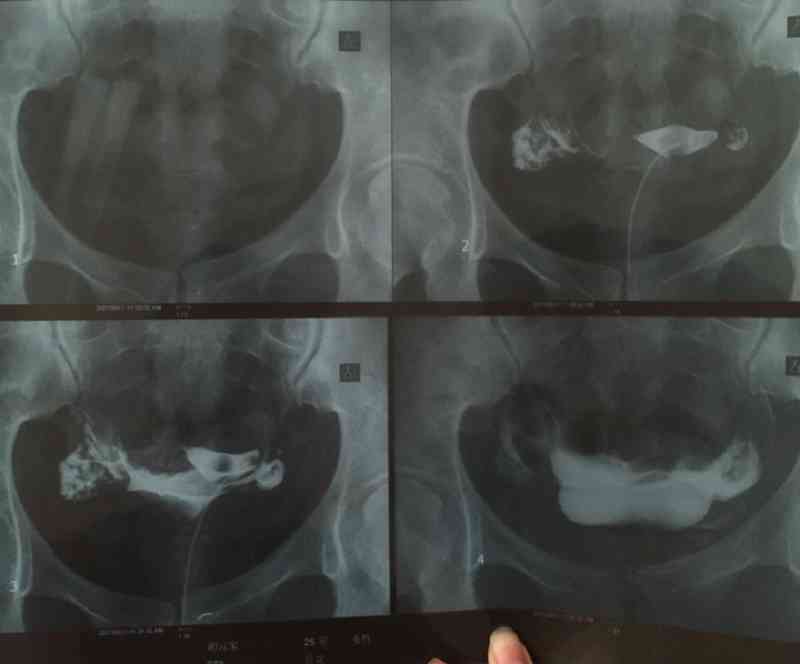

宫外孕手术后输卵管一侧堵塞,一侧通而不畅要怎样治疗?

我去年怀过一次,但是在停经四十多天做B超检查的时候,医生说是宫外孕,所以就做了宫外孕手术,术后到现在快一年多了,再没怀过孕,去医院做输卵管造影,医生说我的输卵管一侧因为宫外孕手术严重堵塞,另一侧通而不畅,想问一下我现在要怎么办才能怀孕?

输卵管造影检查痛苦吗

输卵管造影检查属于有创检查,可能会导致女性下体出血,疼痛等症状出现,对于输卵管堵塞的女性来说这项检查是比较痛苦的,但是如果输卵管是通畅的,那么输卵管造影检查并不痛苦,也不会引起疼痛 ...